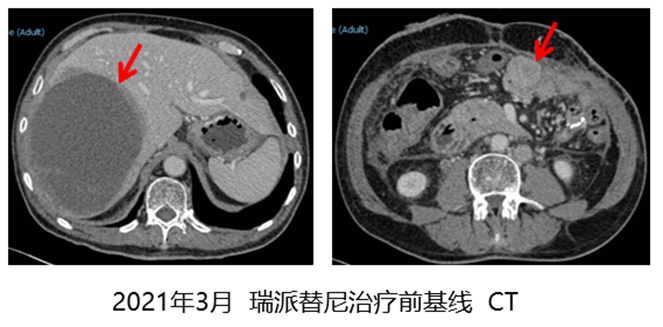

因肝转移灶破裂出血,分别于2020年8月和9月在外院行“经皮肝肿瘤超选择载药微球栓塞术”,术后给予伊马替尼600mg/d。2021年3月疾病进展,CT结果显示:肝右叶见一巨大低密度区,大小约14.2cm×10.0cm×12cm,右下腹壁见造瘘影,左腹术区条索影,周围软组织增多,附近与肠道分界欠清肿块影,大小约3.5cm×3.3cm。

瑞派替尼治疗期间的最佳疗效为疾病稳定(SD),2023年5月治疗25个月后,CT结果显示:肝右后叶见巨大囊实性肿块,肿块大小约12.1cm×10.3cm×12.6cm,右侧腹壁横结肠造瘘,造瘘口区肠壁未见明显增厚,左侧腹壁软组织增厚,肿胀,与邻近降结肠,空肠粘连,吻合口分界不清。疾病仍稳定。直到2023年11月CT结果显示:肝右叶肿块大小约13.7cm×12.3cm×13.8cm,切口旁大网膜类圆形肿块影,大小约2.3cm×3.0cm。邻近空肠受压,局部分界不清,明显强化。疾病进展出组,瑞派替尼治疗时间为31个月